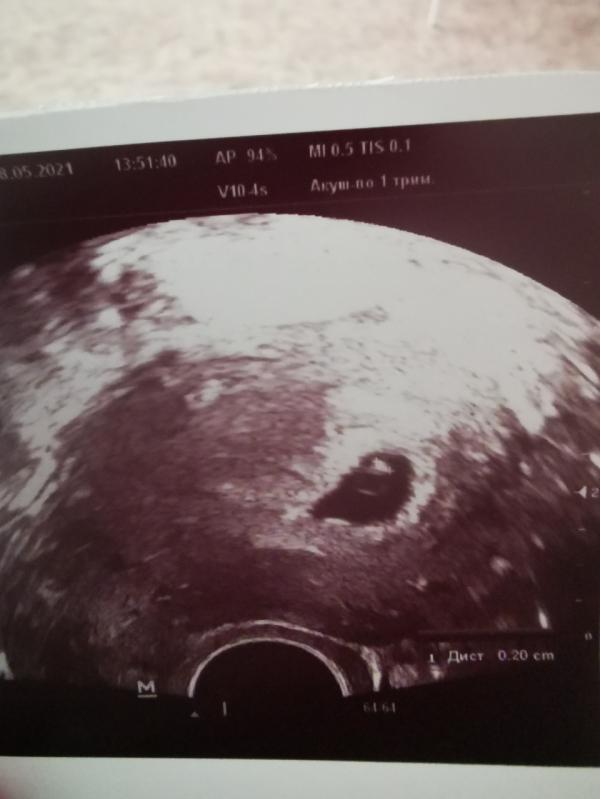

Второе, фото малыша в 5.4 недели